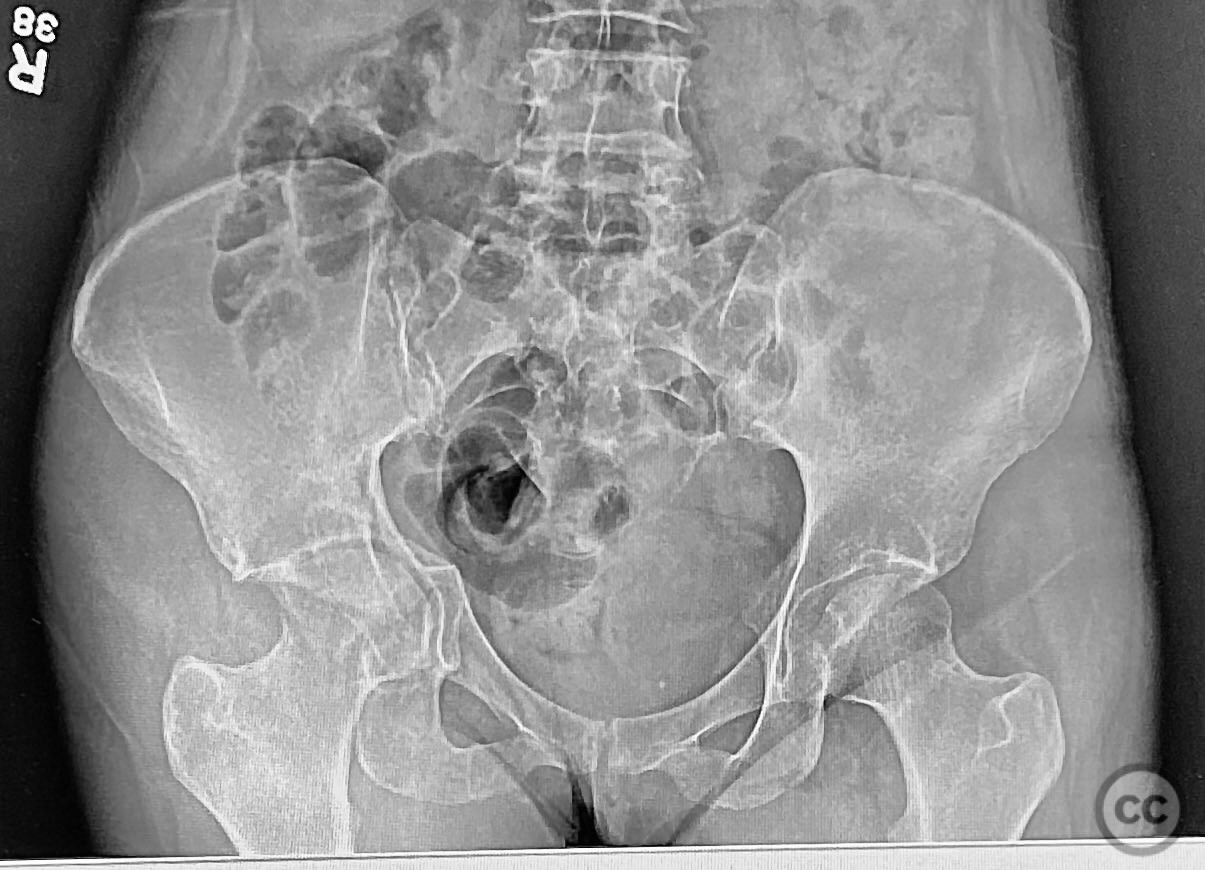

Clinical and radiological findings:  The patient sustained an acetabular fracture with a rare posterior medial dome impaction fragment, as demonstrated on AP pelvic radiographs obtained in skeletal traction. Surface renderings and axial CT images revealed multiple incomplete fracture lines, including a rhomboid-shaped cortical fragment adjacent and proximal to the anterior column/wall fragment. Coronal and sagittal reconstructions further delineated the impacted articular fragment and its relationship to the surrounding acetabular dome. The fracture pattern is classified as AO/OTA 62B3 (associated both-column fracture with dome impaction).

Planning remarks:  The preoperative plan involved an ilioinguinal approach to the acetabulum, utilizing the intrapelvic interval for initial reduction and stabilization of the posterior column with a contoured intrapelvic plate. Sequential reduction of the anterior column and direct management of the impacted dome fragment were planned, facilitated by temporary removal of the rhomboid cortical fragment.